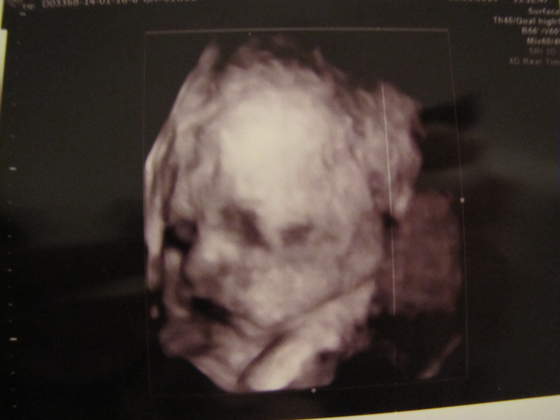

ja nawet dziś na usg leżałam na boku, lekarko powiedziała że jej pacjetki notorycznie mdleją jak na koniec ciązy bada na plecach.